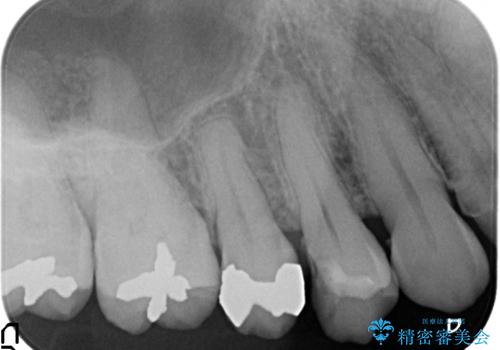

- 右上4番目の歯がしみるといらっしゃった方の症例です。

古い樹脂を除去後、セラミックインレーによる修復を行いました。

虫歯治療は虫歯の進行度によって処置が変わってきます。

虫歯が小さければ、インレー・クラウン等による修復・補綴処置を行うだけで済みます。

しかし虫歯が大きくなると神経処置や抜歯等をしなければならない場合もあります。